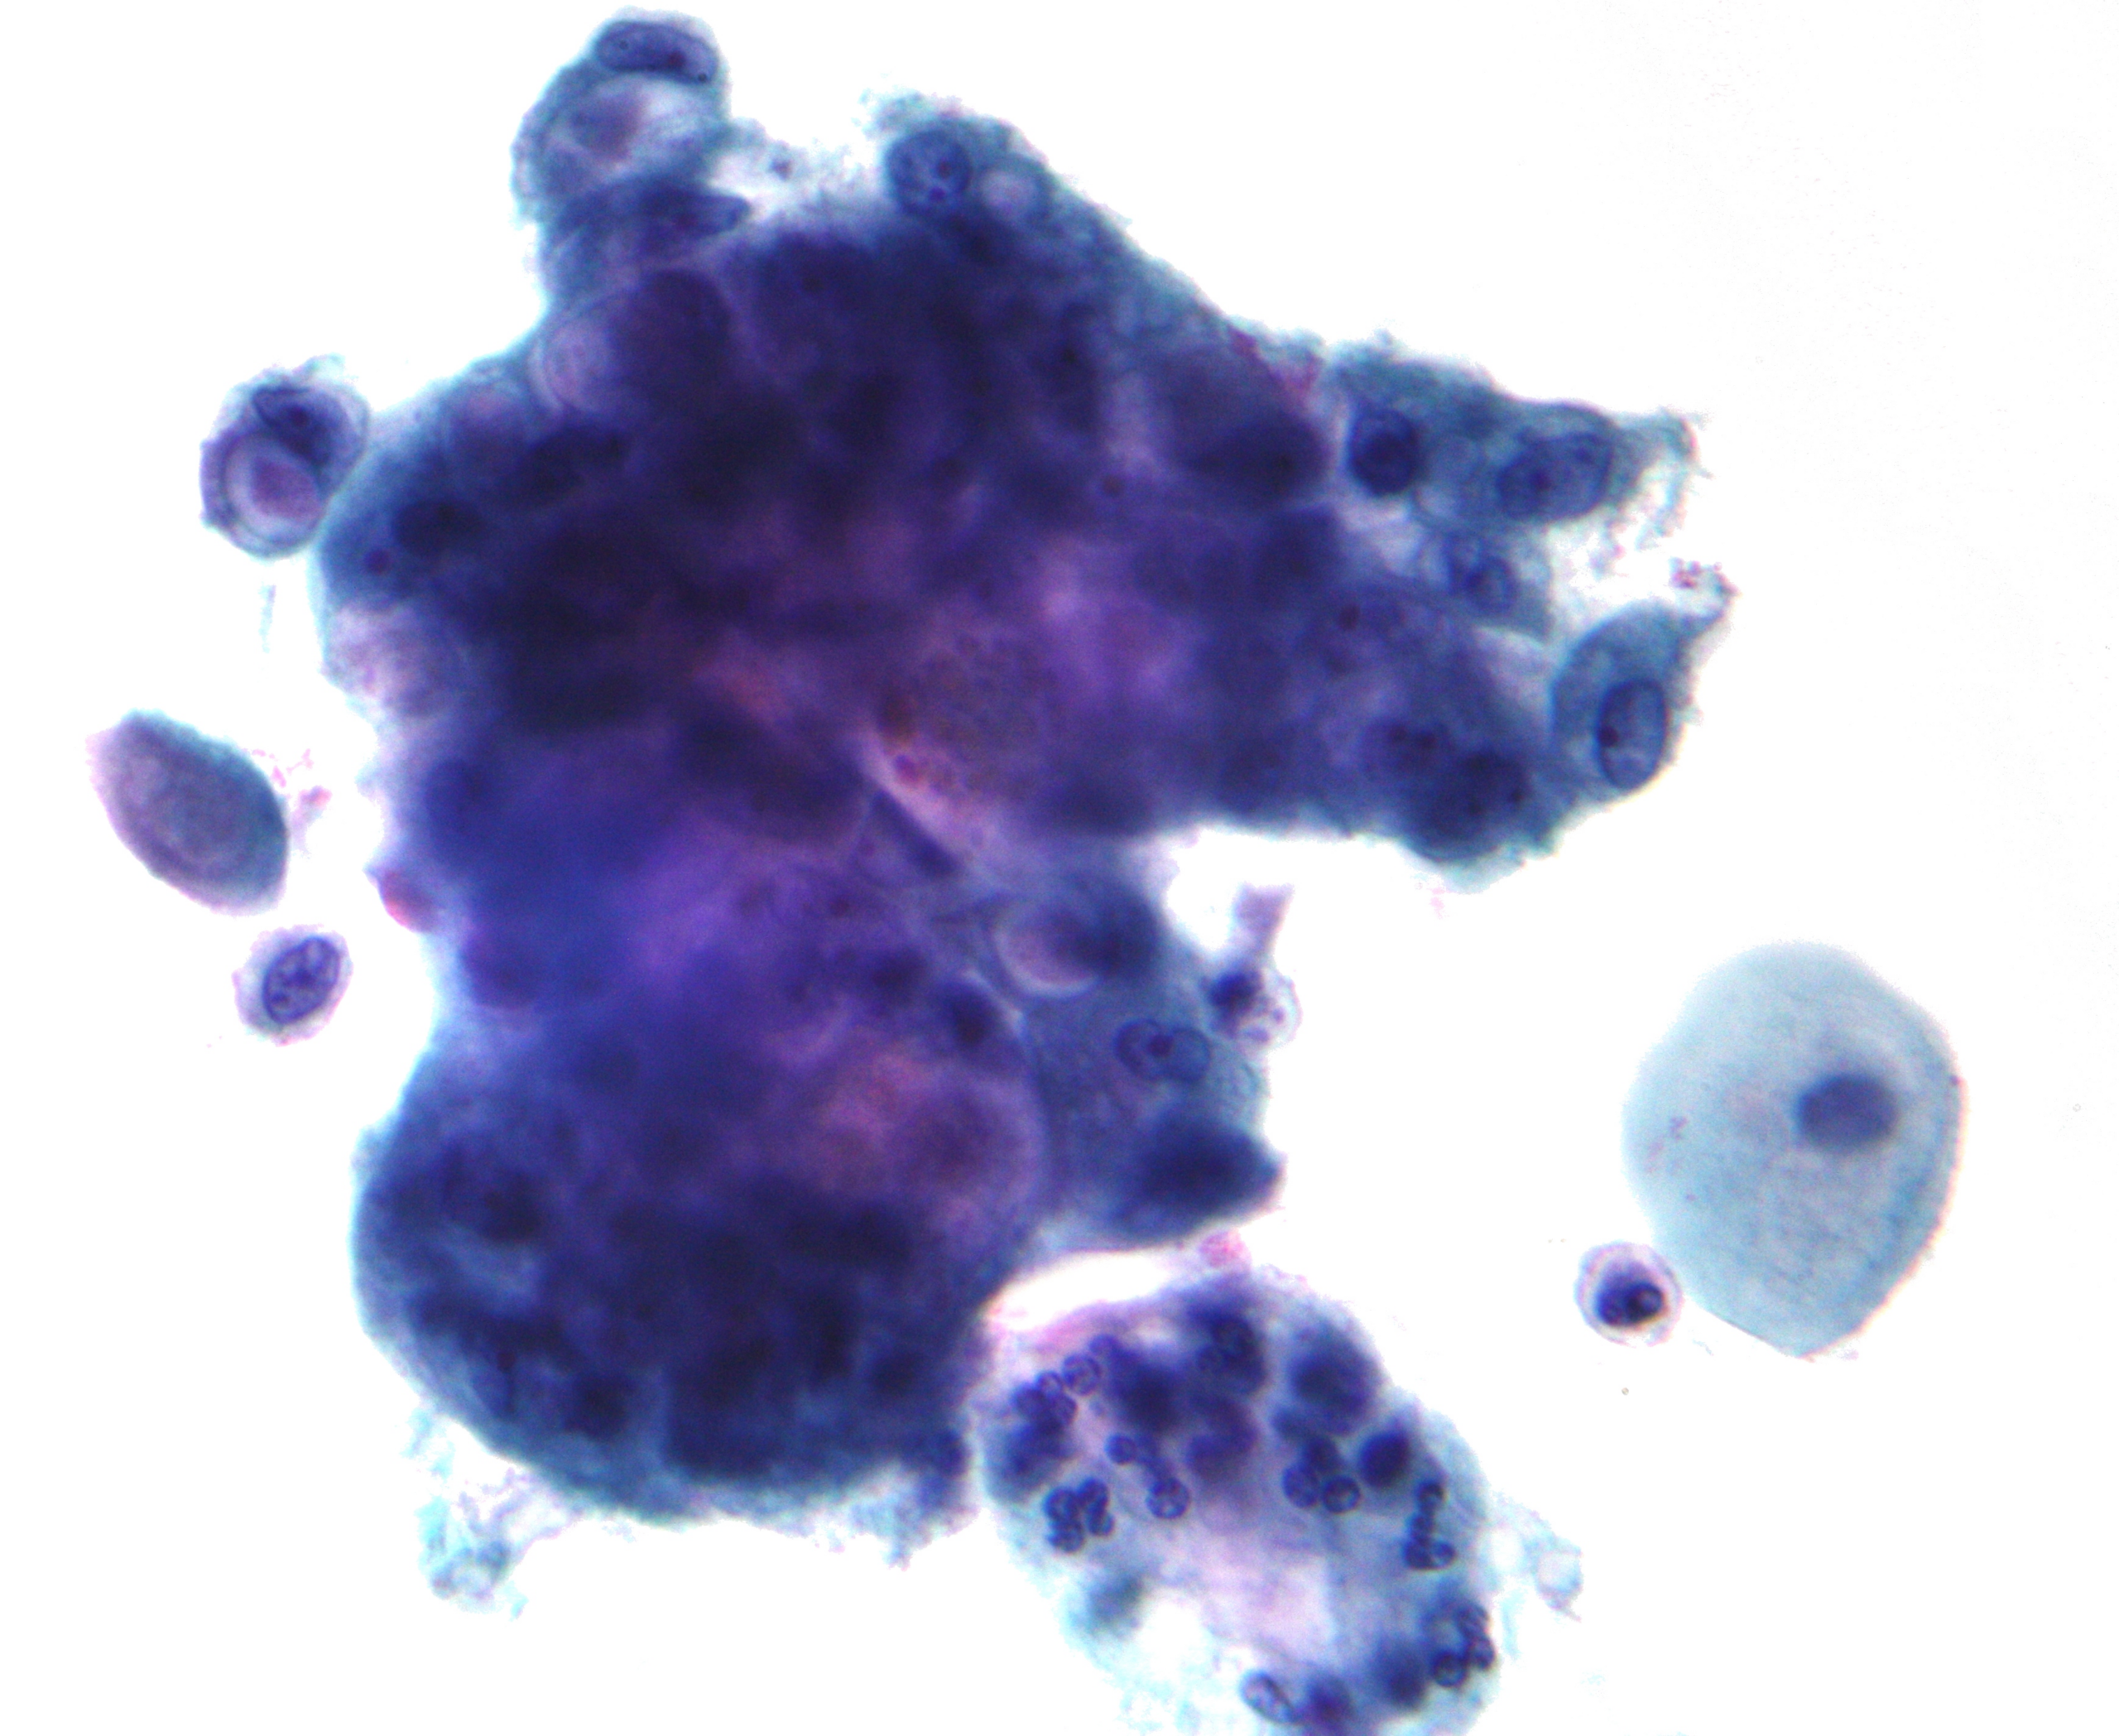

High-grade squamous intraepithelial lesion (HSIL or HGSIL) indicates moderate or severe cervical intraepithelial neoplasia or carcinoma in situ. It is usually diagnosed following a Pap test. In some cases these lesions can lead to invasive cervical cancer, if not followed appropriately.[citation needed]

HSIL does not mean that cancer is present. Of all women with HSIL results, 2%[8] or less[9] have invasive cervical cancer at that time, however about 20% would progress to having invasive cervical cancer without treatment.[10] To combat this progression, HSIL is usually followed by an immediate colposcopy with biopsy to sample or remove the dysplastic tissue. This tissue is sent for pathology testing to assign a histologic classification that is more definitive than a Pap smear result (which is a cytologic finding). HSIL generally corresponds to the histological classification of CIN 2 or 3.[citation needed]